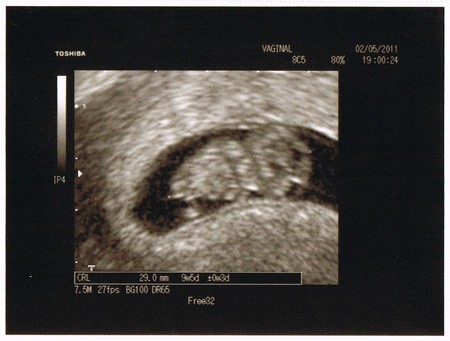

Wróciłam od lekarza, założoną mam kartę ciąży i jest wszystko w porządku. Kosmita ma 3 cm i jest zaskakująco ruchliwy jak na takie małe stworzonko :)

A to, jak to mój mąż określił, żuczek: 02_05s.jpg